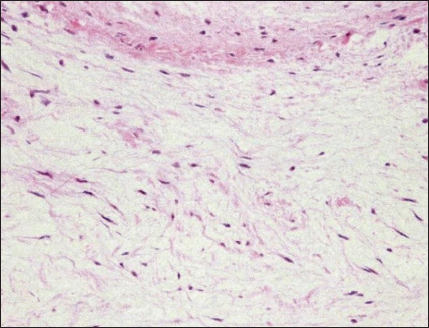

Histopathological examination

Haematoxylin and eosin staining showed spindle-shaped fibroblast-like cells sparsely distributed throughout a faintly eosinophilic myxoid matrix (Fig. 5). The tumour was diagnosed as a myxoma (mesenchymal benign tumour), and histopathology confirmed tumour-free margins.

Fig. 5. Histopathology of the cardiac myxoma. Spindle-shaped fibroblast-like cells are sparsely distributed throughout a faintly eosinophilic myxoid matrix. Haematoxylin and eosin, 200× magnification.